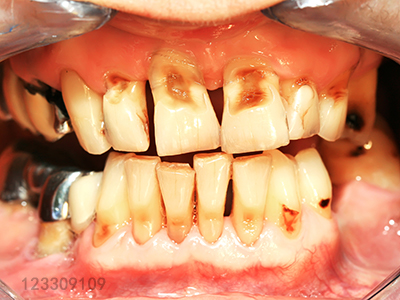

牙周病指的是发生在牙周组织的疾病,包括发生在牙龈组织的牙龈病和殃及深层牙周组织的牙周炎两大类。它不仅会使牙龈、牙槽骨萎缩,最后还会使牙齿松动、脱落。但它的早期症状不易被人察觉,发展比较缓慢,等到发现问题不对了,为时已晚。因为牙周组织被破坏后是不可逆的,所以对于牙周病,预防和早发现非常重要。

牙周病初期的症状和对人的影响都比较微小,但如若在此时发现并积极治疗,很大程度上可以恢复牙周健康,拖得越晚,治疗就会越复杂。